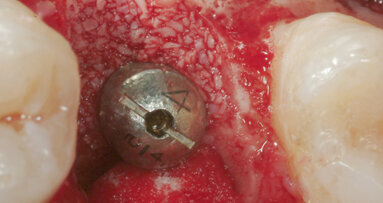

Le estrazioni sono state eseguite con tecnica chirurgica delicata tramite l’utilizzo di leve e pinze, senza eseguire osteotomia e senza danneggiare i tessuti perialveolari. Una volta estratto l’elemento dentario, all’interno dell’alveolo post-estrattivo è stato posizionato un blocchetto di Biopad®; per agevolarne la stabilizzazione è stato dato un punto a materassaio incrociato.

A 20 minuti dalle estrazioni è stata controllata la stabilizzazione del coagulo e i pazienti sono stati dimessi.

Nessuno dei dieci pazienti ha avuto complicanze emorragiche post-operatorie e a 7 giorni tutti i pazienti mostravano segni di epitelizzazione parziale, in 4 casi completa, degli alveoli post-estrattivi.

Nonostante si tratti di soli 10 casi clinici per un totale di 22 estrazioni e di uno studio osservazionale, il Biopad® si è dimostrato essere un buon presidio emostatico. Infatti, pur non avendo sospeso in nessun caso la terapia antiaggregante, non si sono verificate complicanze emorragiche o coaguli esuberanti al controllo.

Possiamo anche segnalare un buon effetto barriera esercitato dal materiale da innesto, che ha garantito un buon isolamento dei tessuti profondi fino alla formazione del tessuto di granulazione negli alveoli più grandi di dimensioni, come per i molari; pur evidenziando un ritardo di guarigione, abbiamo potuto rilevare come il collageno sia stato utile per la migrazione delle cellule epiteliali fino alla chiusura totale dei difetti senza mai manifestare alveoliti.